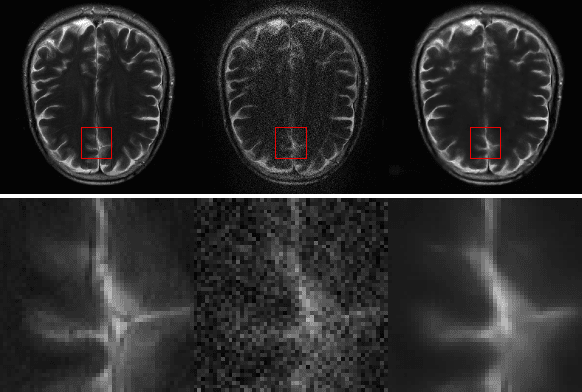

Abstract:k-space undersampling is a standard technique to accelerate MR image acquisitions. Reconstruction techniques including GeneRalized Autocalibrating Partial Parallel Acquisition(GRAPPA) and its variants are utilized extensively in clinical and research settings. A reconstruction model combining GRAPPA with a conditional generative adversarial network (GAN) was developed and tested on multi-coil human brain images from the fastMRI dataset. For various acceleration rates, GAN and GRAPPA reconstructions were compared in terms of peak signal-to-noise ratio (PSNR) and structural similarity (SSIM). For an acceleration rate of R=4, PSNR improved from 33.88 using regularized GRAPPA to 37.65 using GAN. GAN consistently outperformed GRAPPA for various acceleration rates.